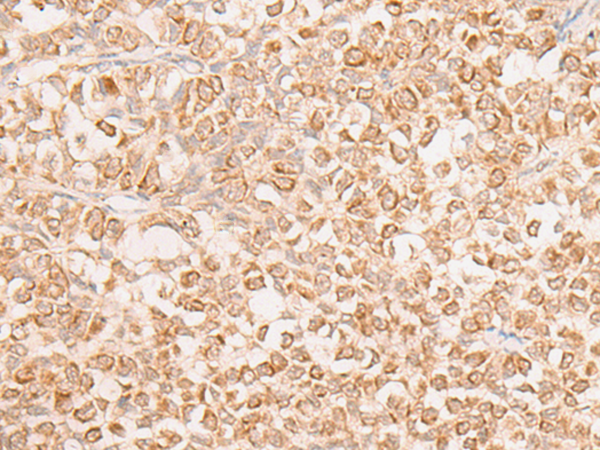

分类: 科研抗体货号: P06464别名: LRAP; L-RAP应用: IHC反应种属: Human